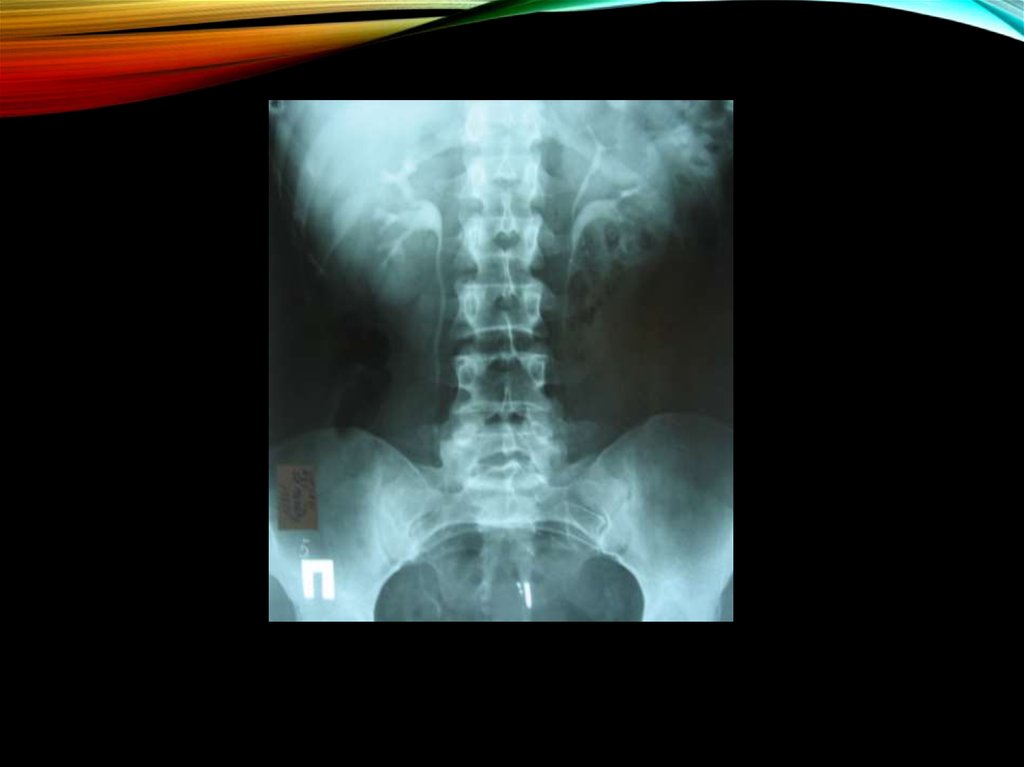

19. Изменения рентгенологической картины:

ИЗМЕНЕНИЯ РЕНТГЕНОЛОГИЧЕСКОЙ

КАРТИНЫ:

экскреторная урография

снижение тонуса верхних мочевых путей

уплощенность и закругленность углов форниксов

сужение и вытянутость чашечек

позднее - деформация чашечек, сближение их

пиелоренальные рефлюксы

пиелоэктазии

асимметрия размеров почек

ретроградная пиелография:

картина гипоплазированной почки;

почечная ангиография (в редких случаях):

уменьшается просвет почечной артерии

периферическое кровоснабжение обедняется

облитерируются мелкие сосуды коркового

вещества.